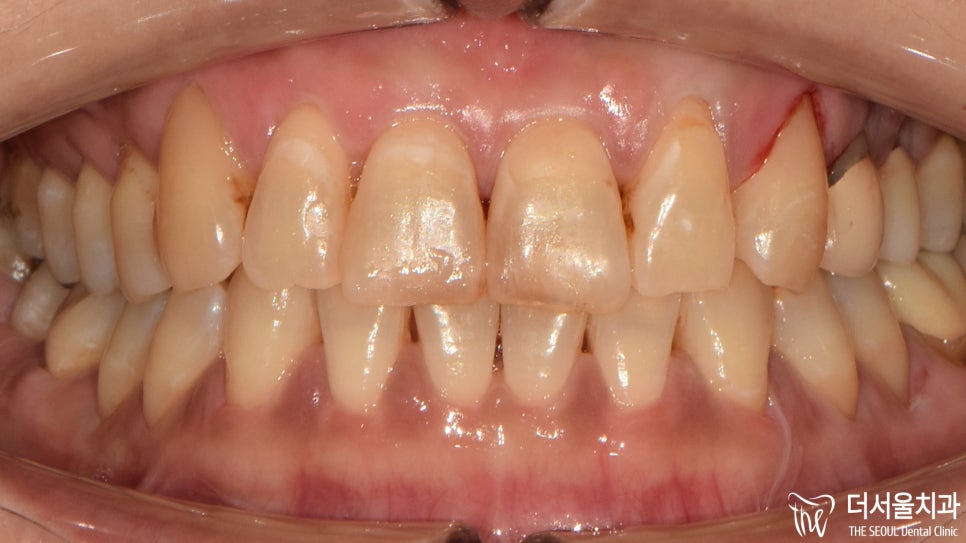

더서울에서 앞니 충치치료 과정을 끝낸 모습입니다.

약간의 출혈이 나타난 곳은

스케일링을 진행했기 때문에 생긴건데요.

치석이 붙어 있는 곳이 떨어져나가면서

소량의 출혈이 발생한 것입니다.

자연스레 회복되니 걱정하지 않으셔도 됩니다^^

검게 썩어있던 곳들이 말끔하게 채워져

좀 더 심미적인 외관을 갖게 되었습니다.

치경부는 접착이 제대로 되지 않는 곳 중 하나라

유독 더 꼼꼼하게 살펴봐야 되는데요.

사용을 하다 떨어지지 않도록

몇차례의 확인을 거쳐 마무리를 도와드렸습니다.